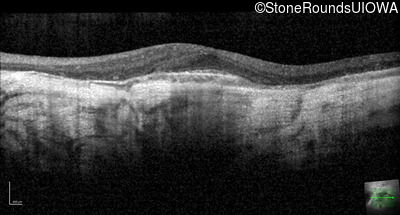

Optical Coherence Tomography - Right - 20/40 -2

Exemplar / OCT Stack